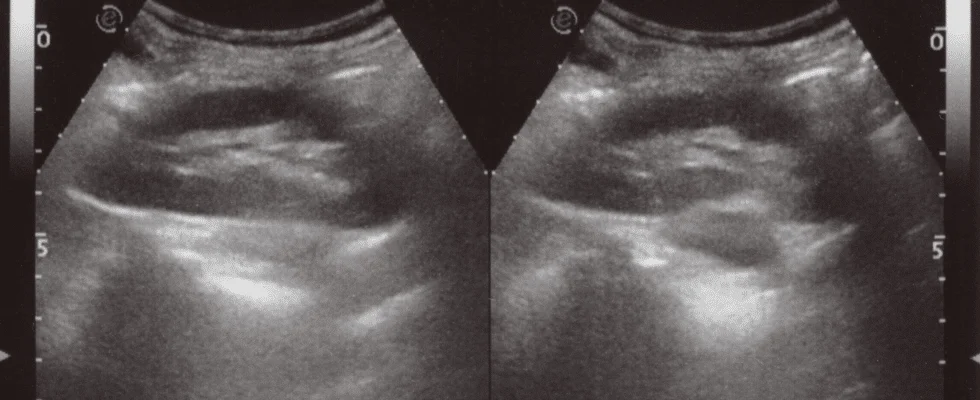

“Cadaveric study investigating the femoral nerve-sparing volume for pericapsular nerve [...]